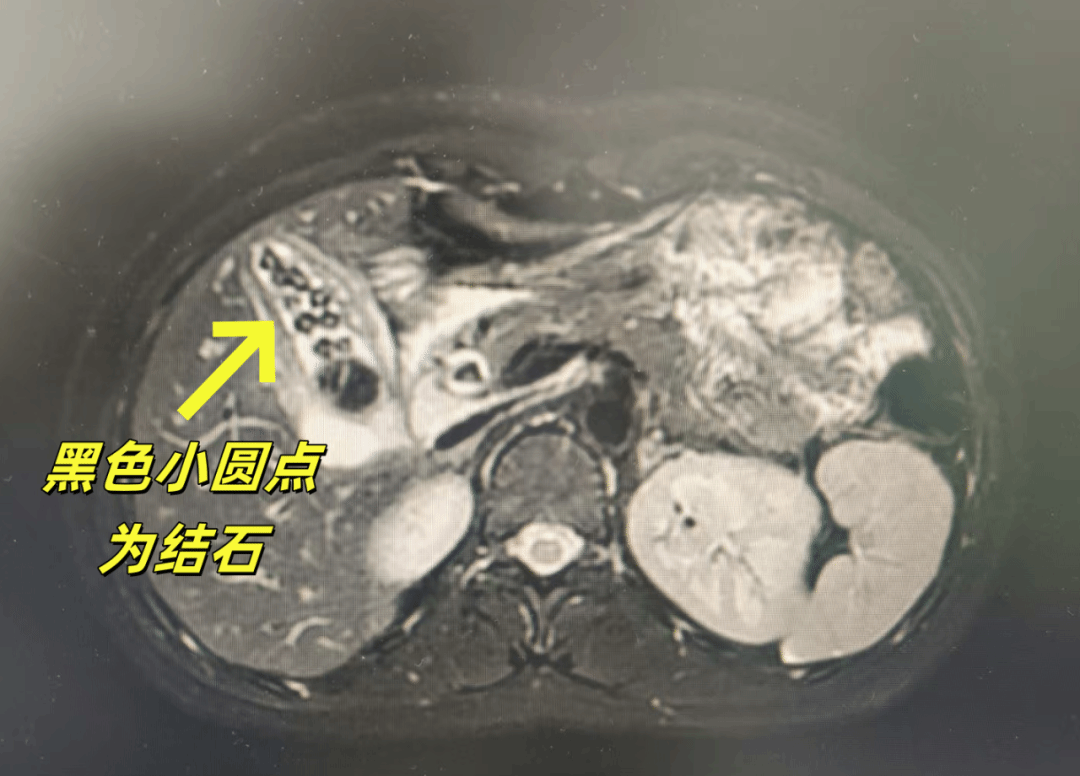

13岁的萱萱(化名)反复腹痛长达4个月,一度被误认为“肠胃炎”。直到来重庆医科大学附属儿童医院检查发现:肝功能严重异常,转氨酶明显升高,影像学结果更令人震惊:胆囊与胆管内布满结石,宛如一个隐藏在体内的“巨石阵”。

胆囊内多发结石

胆管内多发结石